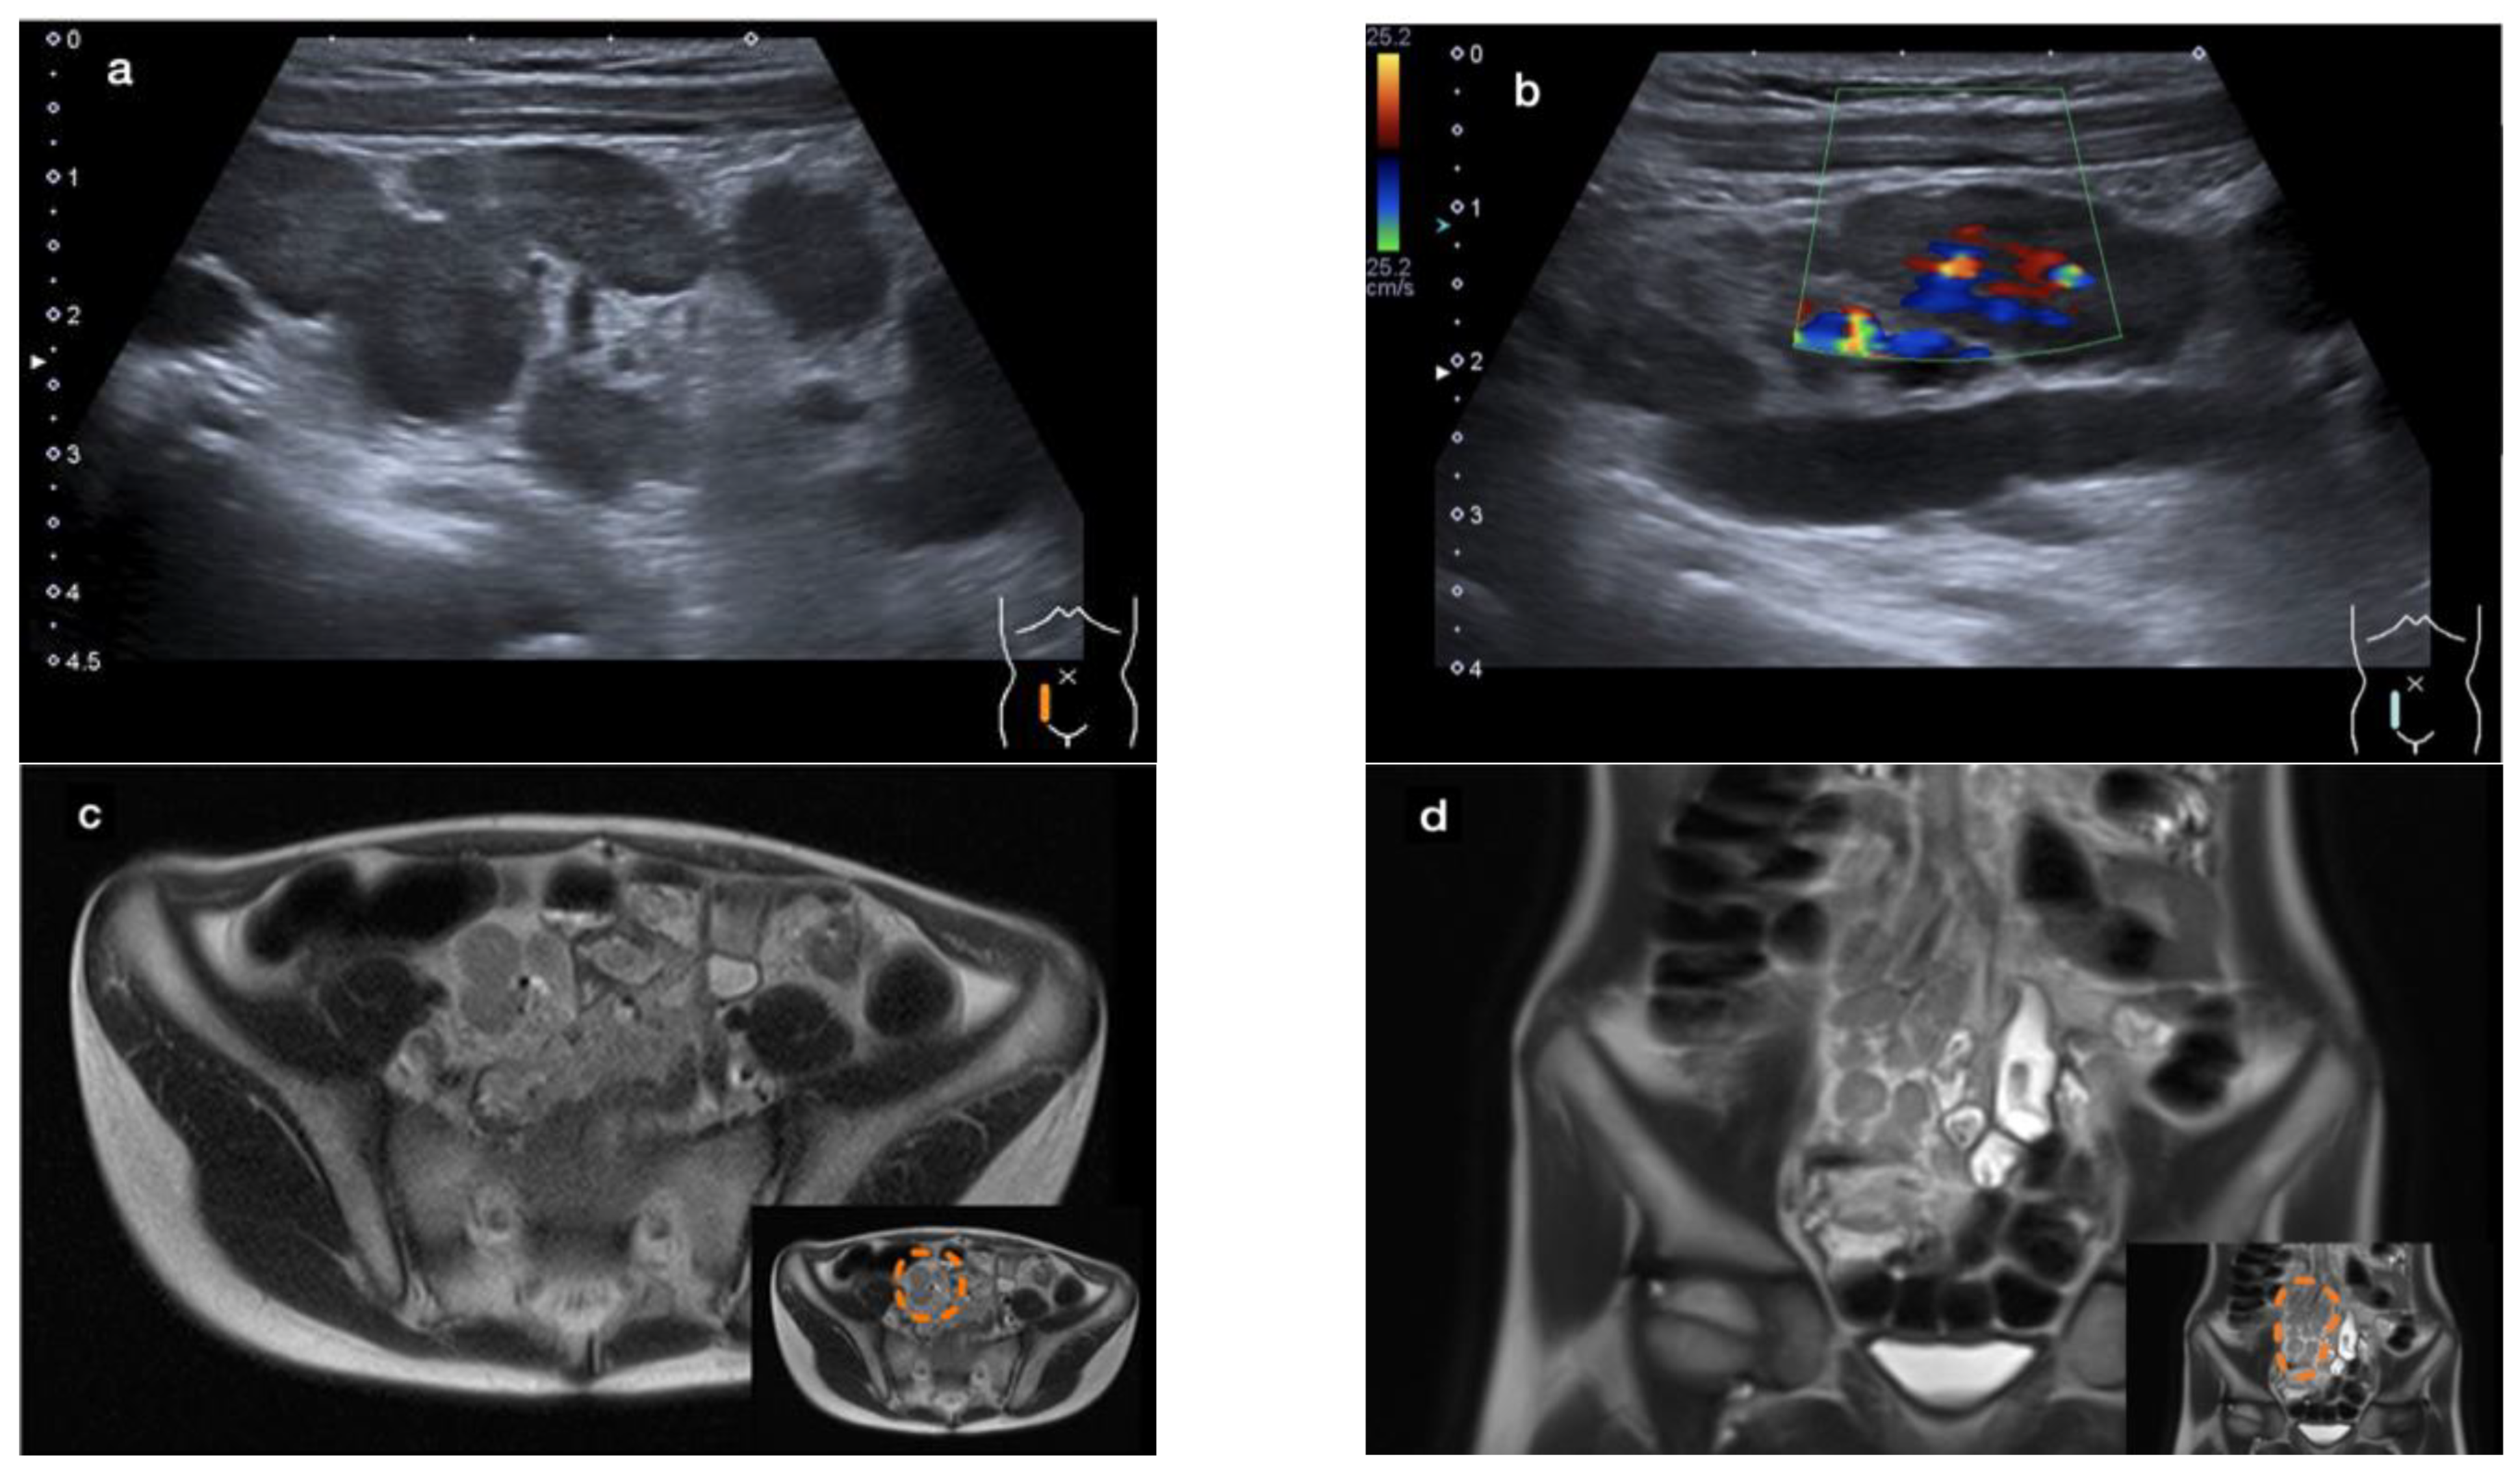

2. Case 1

2.3. Diagnostic Evaluation